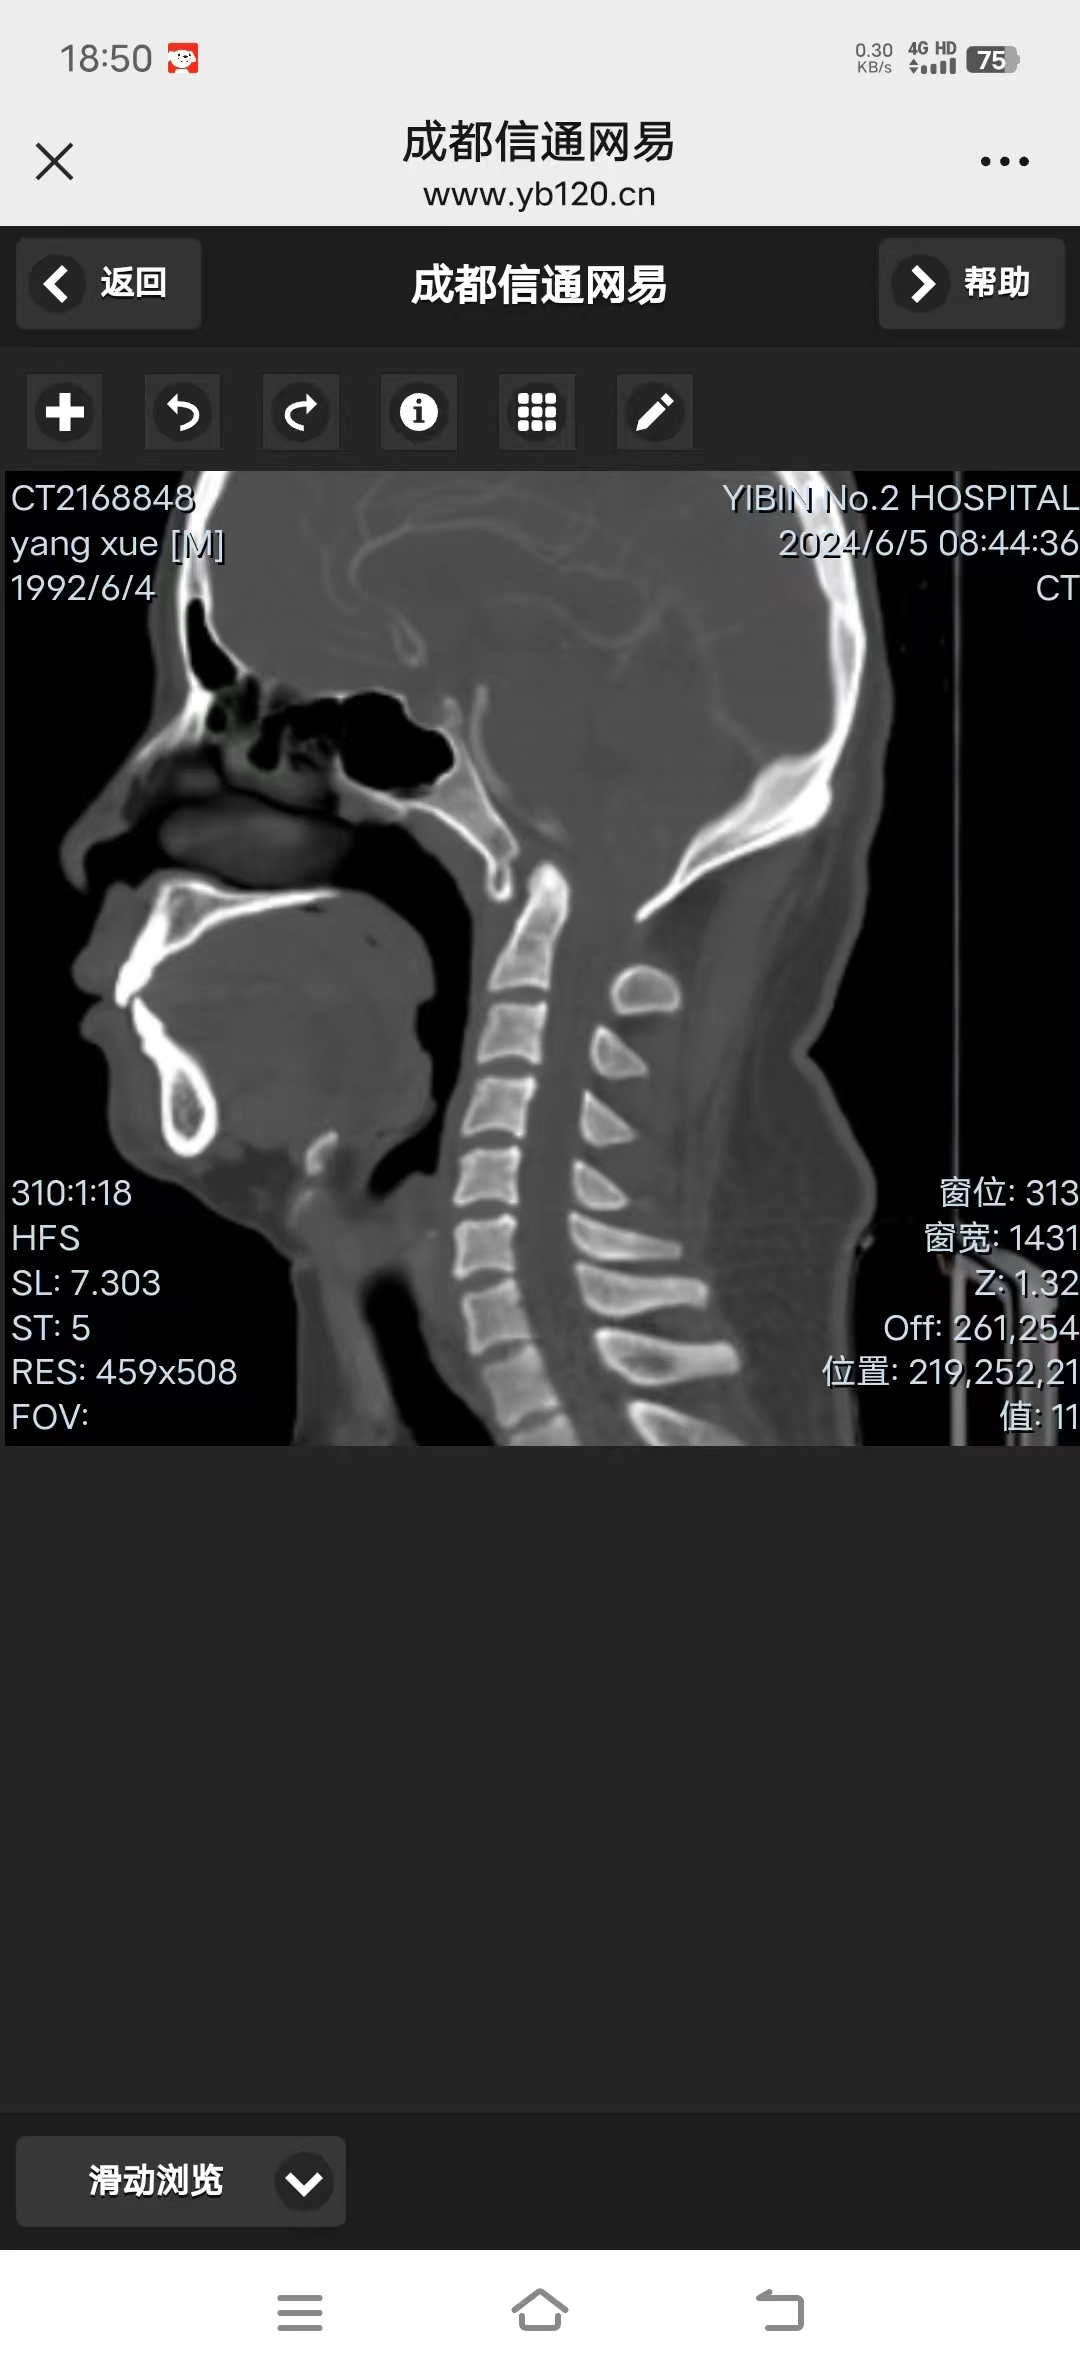

• 诊断:寰枢椎脱位、颅底凹陷、小脑下疝、脊髓空洞

• 影像: